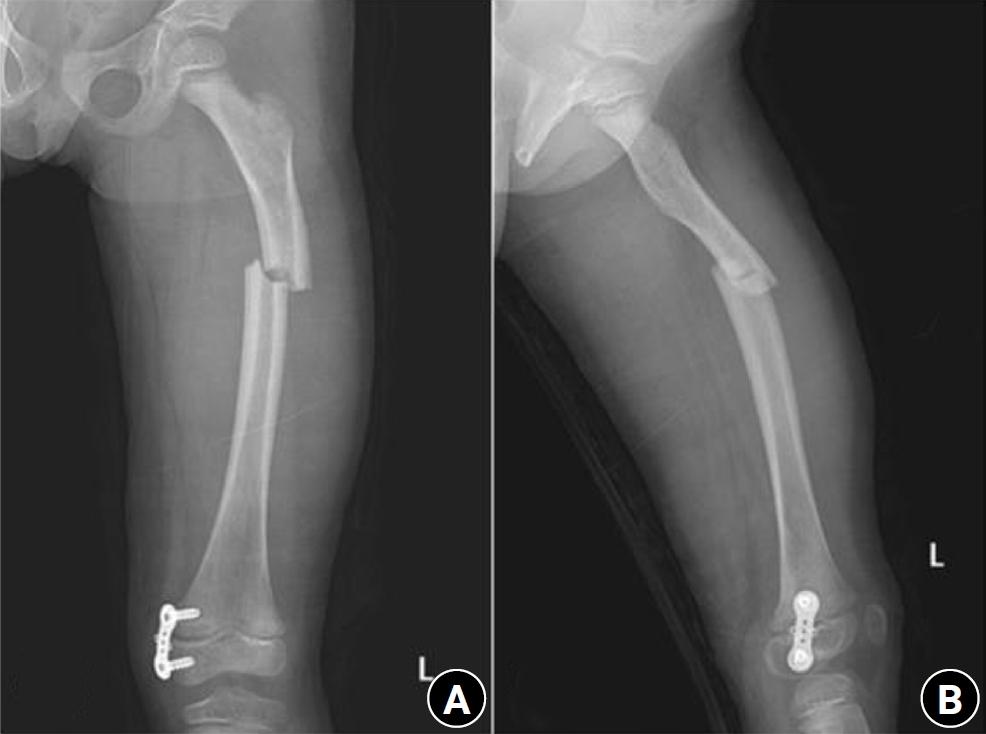

Fig. 4.

Prefracture radiograph of an 8-year-old female patient who presented with a proximal one-third fracture of the left femur (bilateral lower-extremity standing anteroposterior view).

jmt-2025-00388f4.jpg

An 8-year-old female patient visited our emergency room complaining of pain in the left thigh that began on the day of her visit. She slipped and directly injured her thigh upon falling to the left. Initial examination revealed normal laboratory findings, including serum calcium levels of 9.0 mg/dL and inorganic phosphorus levels of 4.7 mg/dL. Radiographic evaluations, including anteroposterior and lateral views of the left femur, demonstrated a transverse irregular fracture line in the proximal one-third area of the left femur, accompanied by lateral cortex hypertrophy. Importantly, the possibility of malignancy or infection as contributing factors to the fracture was considered low. Two years prior, the patient had visited the pediatric department of our hospital due to concerns about her height, which was below that of her peers. Following genetic testing, she was diagnosed with osteogenesis imperfecta and has since been monitored by both the pediatrics and orthopedics departments. At that time, lateral bowing of both femurs was observed in both lower extremities during standing anteroposterior evaluations (Figs. 4, 5). She had previously undergone epiphysiodesis on both femurs due to genu valgum. After diagnosis, the patient underwent open reduction and internal fixation using an ender nail. Follow-up evaluations indicated successful bone union at the fracture site.